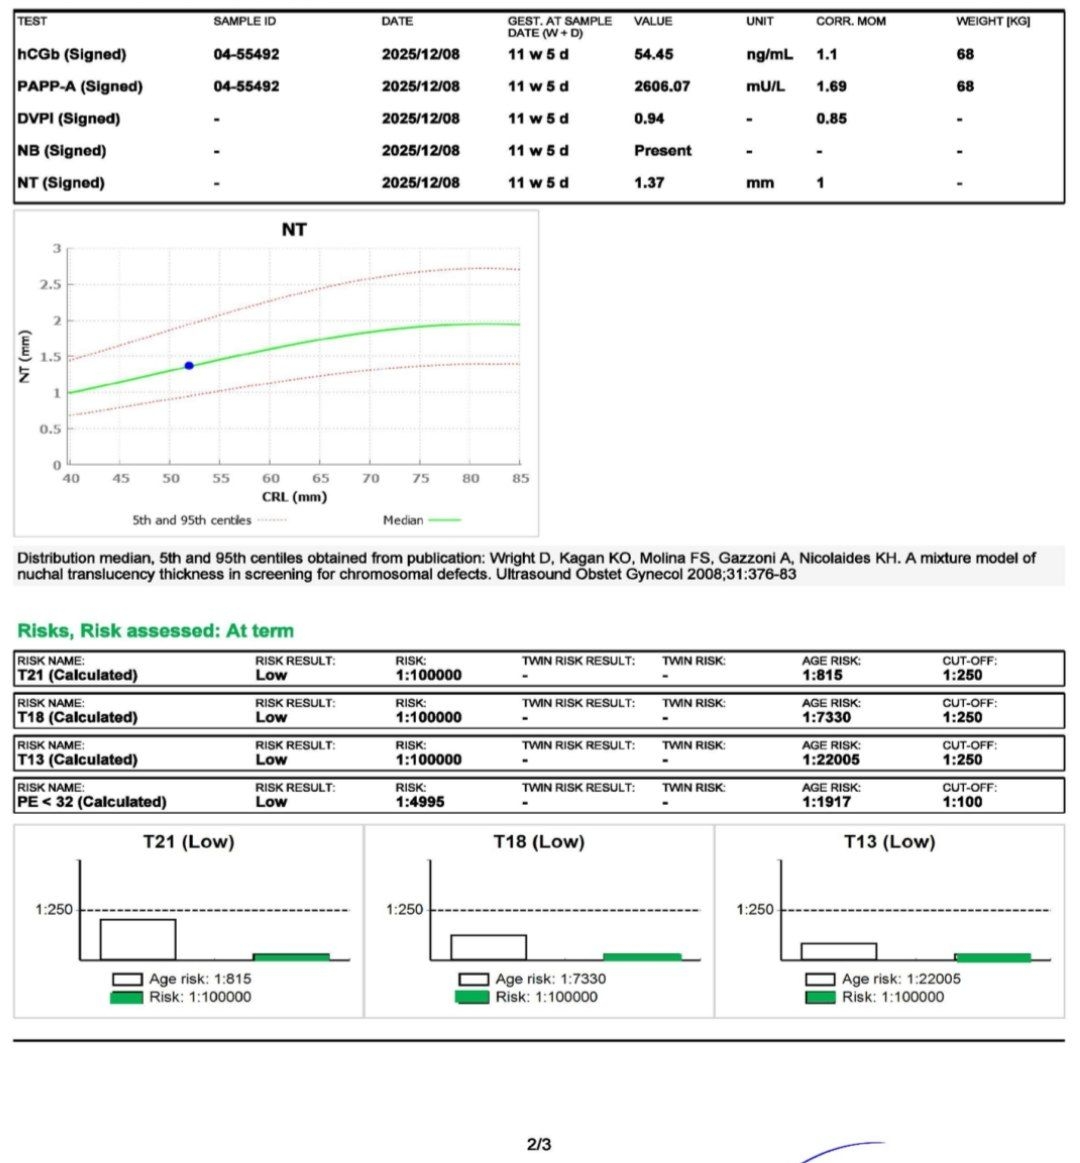

در سونوگرافی شما تمام موارد بررسی شده از جمله وضعیتجنین ، ان تی، حجم مایع آمنیوتیک و ضربان قلب در محدوده نرمال قرار دارد و از این بابت جای نگرانی نیست. در مورد جفت نیز جایگاه آن لولایینگ یعنی حاشیه ای گزارش شده است که نشان میدهد جفت اندکی به دهانه رحم نزدیک است. در چنین مواردی در اغلب مواقع با افزایش سن حاملگی و بزرگ شدن رحم، دیواره های آن کشیده شده و بنابراین جفت نیز به سمت بالا کشیده می شود و مشکلساز نخواهد شد اما فعلا میزان استراحت خود را تا جایی که می توانید افزایش دهید. از انجام دادن کارهای سنگین و بلند کردن وسایل با وزن بالا اجتناب کنید. پیاده روی طولانی نداشته باشید. نزدیکی و دخول کامل متوقف شده و همچنین شخص شما به ارگاسم نرسید، تحریک و دستکاری نوک سینه ها انجام نشود. تلاش کنید تا دچار یبوست نشوید از سرویس بهداشتی فرنگی استفاده نمایید و دوش آب گرم طولانی مدت نگیرید، به علاوه ریسک محاسبه شده برای سندروم های ژنتیکی تریزومی ۲۱ و تریزومی ۱۸ و 13 همگی در محدوده کم خطر قرار داشته و منفی هستند. در حال حاضر نیاز به هیچ بررسی دیگری از جمله غربالگری مرحله دوم نیست و فقط در هفته هجده بارداری مانند تمام مادران سونوگرافی آنومالی اسکن برای ارزیابی ساختارهای بدن جنین و همچنین آزمایش Ntd screen برای ارزیابی اختلالات لوله عصبی (این بررسی ضرورت جدی انجام ندارد و فقط در صورت صلاحدید پزشکتان درخواست گردد) انجام دهید🌹